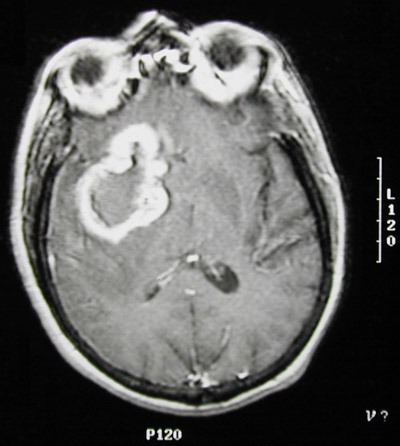

| This axial view MRI scan demonstrates a large glioblastoma multiforme of the right cerebral hemisphere. Note that there is central lucency from necrosis and a brightly enhancing rim that is irregular, typical for this highly malignant neoplasm of the brain. |